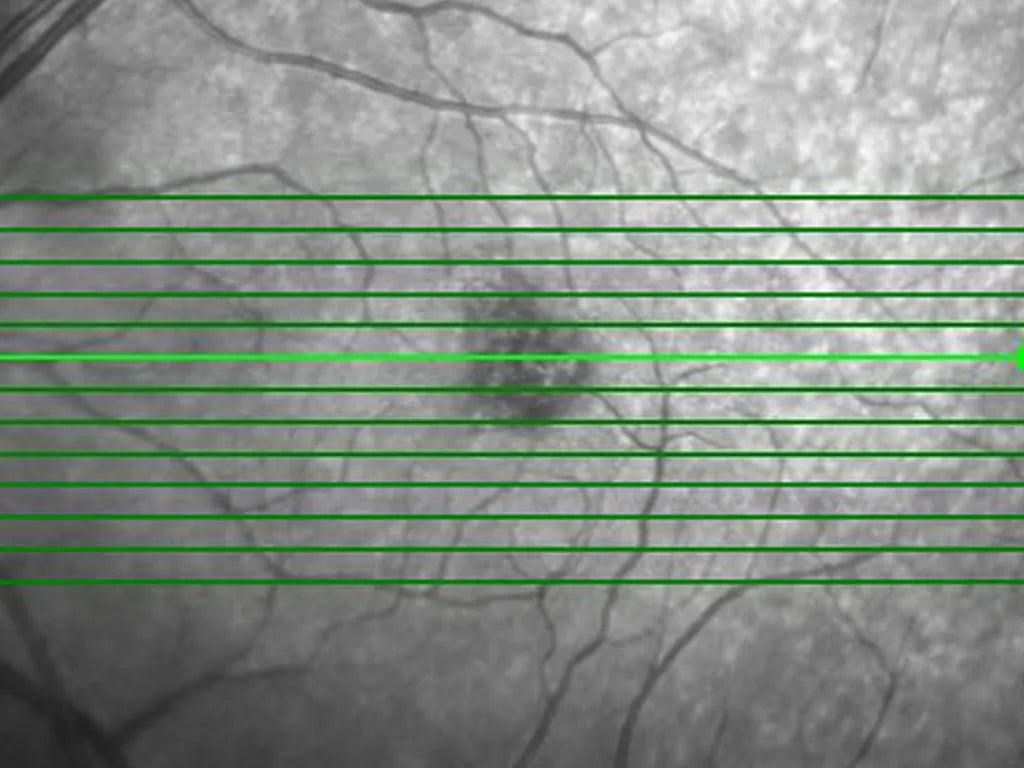

Optical Coherence Tomography (OCT) has revolutionized medical imaging, industrial inspection, and scientific research, providing high-resolution, cross-sectional images with non-invasive techniques. Whether for ophthalmology, dermatology, cardiology, or materials science, OCT requires high-speed, precision beam scanning to capture clear, detailed images.

The Saturn series of optical scanners provides high-frequency raster scanning and precise beam deflection, making them ideal for OCT in medical diagnostics, industrial inspection, and scientific imaging. These scanners deliver: